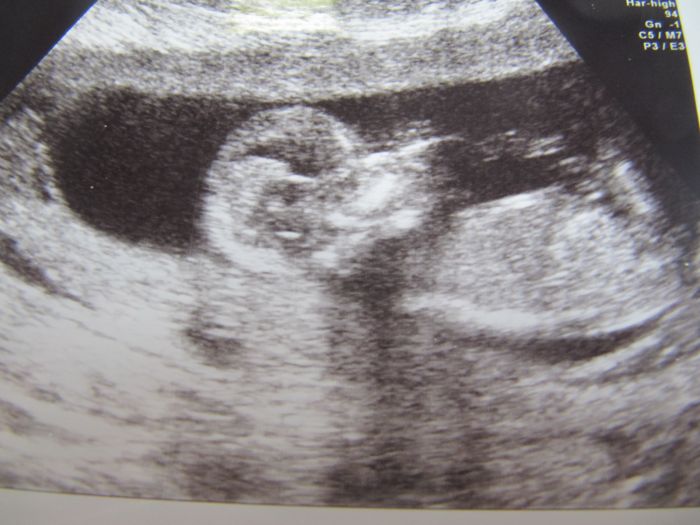

Přidávám včerejší fotečku prďouska

Včera jsem byla na screeningu a výsledky dopadly nad očekávání dobře vzhledem k mým 40. letům, tak jsem si hooodně oddychla. Paní doktorka prvně miminko budila, aby se otočilo k ní a pak začalo tak řádit, že je vůbec nemohla pořádně zaměřit a zkontrolovat, co potřebovala, tak jsme tam byli dost dlouho, než naměřila, co potřebovala. Proto jsme se s přítelem ani neptali na pohlaví našeho prďouska

Podle UTZ jsem 13+2 dnes a termín sedí podle MS na 8.12.